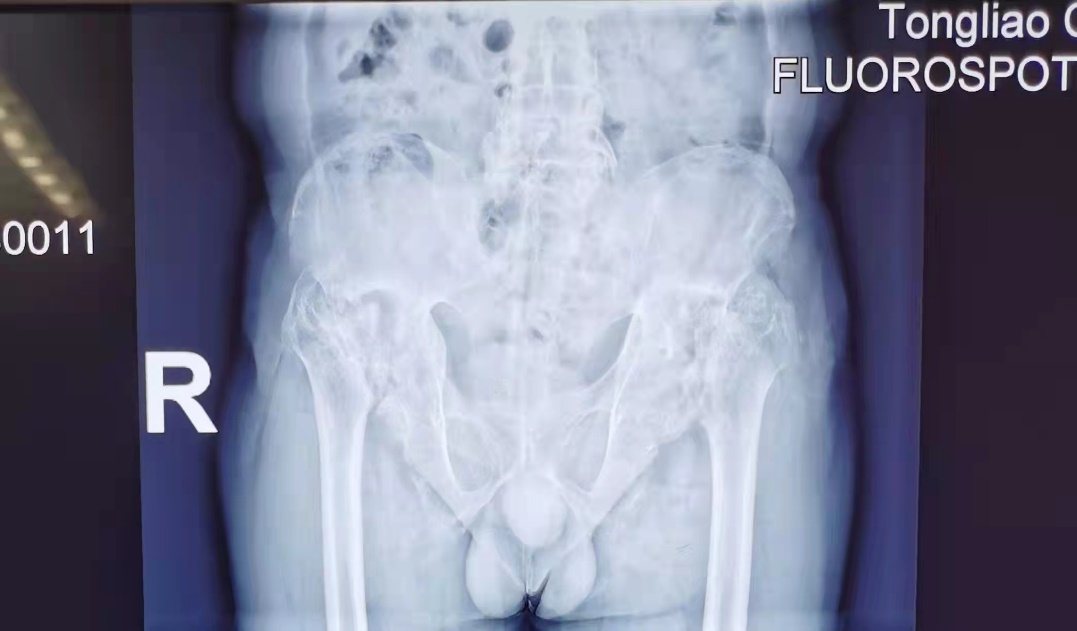

患者男性,45岁,患有强直性脊柱炎多年,双侧髋关节活动受限逐渐加重,该患者为民政重点扶贫救治对象。经住院后详细的术前检查评估,患者双侧髋臼股骨头缺损且髋臼为巨大型缺损,无法用常规髋关节假体完成手术。故决定采用目前国际国内最前沿的3D打印技术打印关节假体,为患者实施手术。